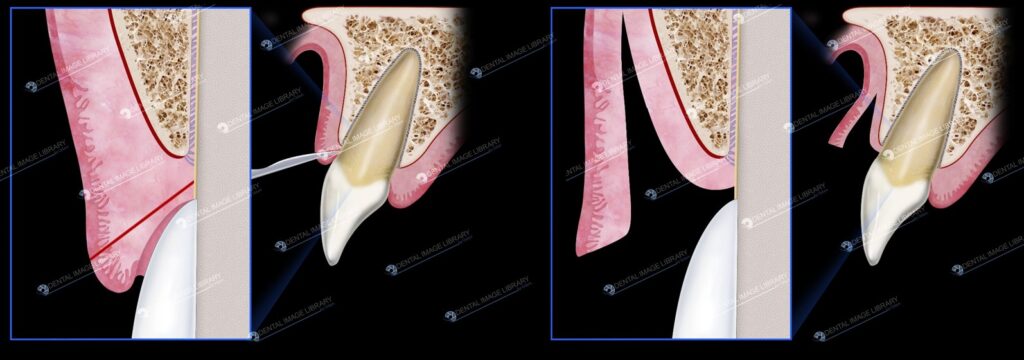

Nghiên cứu trên động vật đã chứng minh rằng các mạch máu nướu có xu hướng tương đối thẳng đứng (hình 2-3).

Do đó, đường rạch nên định hướng đúng theo chiều dọc để giảm thiểu việc cắt đôi các mạch này. Nhờ đó sẽ làm giảm chảy máu trong khi phẫu thuật và cũng tối đa hóa việc cung cấp máu cho các mô xung quanh vạt. Duy trì đáy vạt ít nhất rộng bằng đường rạch phía thân răng để đảm bảo cung cấp máu.

Nhìn chung, lưu lượng máu đáng kể hiện diện trong mô nướu ngăn ngừa mọi nguy cơ hoại tử vạt vì thiếu máu tại chỗ thứ phát do nguồn cung cấp máu bị tổn thương. Sự tưới máu qua vạt đã được chứng minh là bị tổn hại ở những vị trí mà tỷ lệ giữa chiều dài và chiều rộng của vạt lớn hơn 2:1 (Patterson, 1968). Trong trường hợp đây là một rủi ro tiềm ẩn, bác sĩ nên mở rộng vạt theo chiều ngang.